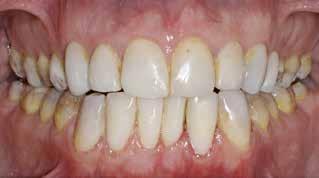

Behandling af lokaliseret anteriort tandslid med fast bidskinne ad modum Bjørn Dahl

Fig. 2. A. Indprøvning af tilpassede Odus Pellakroner anvendt som matricer. B. For at opnå god æstetik blev Odus Pellakronerne fyldt med plast med lagteknik: a) 1. lag af transparent plast (emalje A1) blev lagt facialt i matricen i en tykkelse på ca. 1 mm. b) 2. lag af opak, men lys plast (dentin A1) blev lagt i den incisale del uden at skubbe til det faciale emaljelag. c) 3. lag af mere opak og med højere chroma i plasten (dentin A3) blev lagt mere gingivalt. d) Den fyldte matrice set apikalt fra, hvor kun 1. og 3. lag er synlige. C. Efter adhæsiv behandling af tænderne blev de fyldte Odus Pellakroner påsat to ad gangen og lyspolymeriseret grundigt både facialt og palatinalt fra. D. Før pudsning palatinalt blev gingivale områder repareret med flowplast, hvor matricerne ikke havde kunnet slutte tæt. E. I forbindelse med pudsning blev højden af kronerne reduceret for at få god faciolingval tykkelse i plasten incisalt og herved øgede mekaniske egenskaber. Fig. 2. A. Testing of adapted Odus Pella crowns used as matrices. B. To achieve good aesthetics, Odus Pella crowns were filled with resin composite using layering technique: a) The 1st layer of transparent resin material (enamel A1) was placed facially in the matrix in a layer of appr. 1mm. b) The 2nd layer of opaque but still light resin material (dentin A1) was placed in the incisal part, without pushing the enamel layer. c) The 3rd layer of more opaqu and a higher chroma in the resin material (dentin A3) was placed more gingivally. d) The filled matrix seen apically, where only the 1st and 3rd layers are visible. C. After adhesive treatment of the teeth, the filled Odus Pella crowns were applied two at a time and thoroughly lightcured both facially and palatinately. D. Before finishing, the gingival areas were repaired with flowable resin material, where the fit of the matrices had been insufficient. E. During finishing the height of crowns was reduced to get a better facio-lingual thickness of the resin material incisally and hereby increase the mechanical properties.

handlingsseance blev der som matricer anvendt Odus Pellakroner (Fig. 2A). De blev tilpasset tænderne approksimalt og facialt og placering indøvet mhp. korrekt kronehøjde, facial prominens og bidhævning på ca. 2 mm palatinalt. Før adhæsiv behandling blev Odus Pellakronerne fyldt med plast (microfil hybridplast med gode mekaniske egenskaber) i emalje og dentinfarver (Fig. 2B) og lagt parat under en lysbeskyttende skærm klar til brug. Dernæst blev emalje-dentin-binding udført på alle seks tænder

og matricer til de to centraler placeret og lyspolymeriseret (Fig. 2C, a). Herefter blev lateral og hjørnetand placeret og polymeriseret én side ad gangen (Fig. 2C, b). Palatinalt, hvor matricerne ikke sluttede tæt gingivalt, blev der repareret med flowplast før salivakontakt (Fig. 2D). Som det fremgår af Fig. 2C, b, var alle tænder for høje incisalt-gingivalt, hvilket var bevidst, fordi en efterfølgende incisal afkortning ville give større faciolingval materialetykkelse og bedre mekaniske egenskaber i plasten (Fig.

2D, E). Palatinalflader og incisalkanter blev pudset til jævn okklusion og artikulation med en bidhævning på ca. 2 mm og et bidplateau palatinalt mhp. aksial belastning og begrænsning af kipning (Fig. 2F, a og b). For at facilitere ekstrusion af præmolarer og molarer blev der udført en let approksimal stripping (Fig. 2G). Der blev ikke efterfølgende anvendt bidskinne med henblik på at forebygge fortsat attrition, fordi forfatterens kliniske erfaring er, at bruksister oftest ophører med at skære tænder, når tandkontakterne ændres fra at være i tandsubstans til plast.